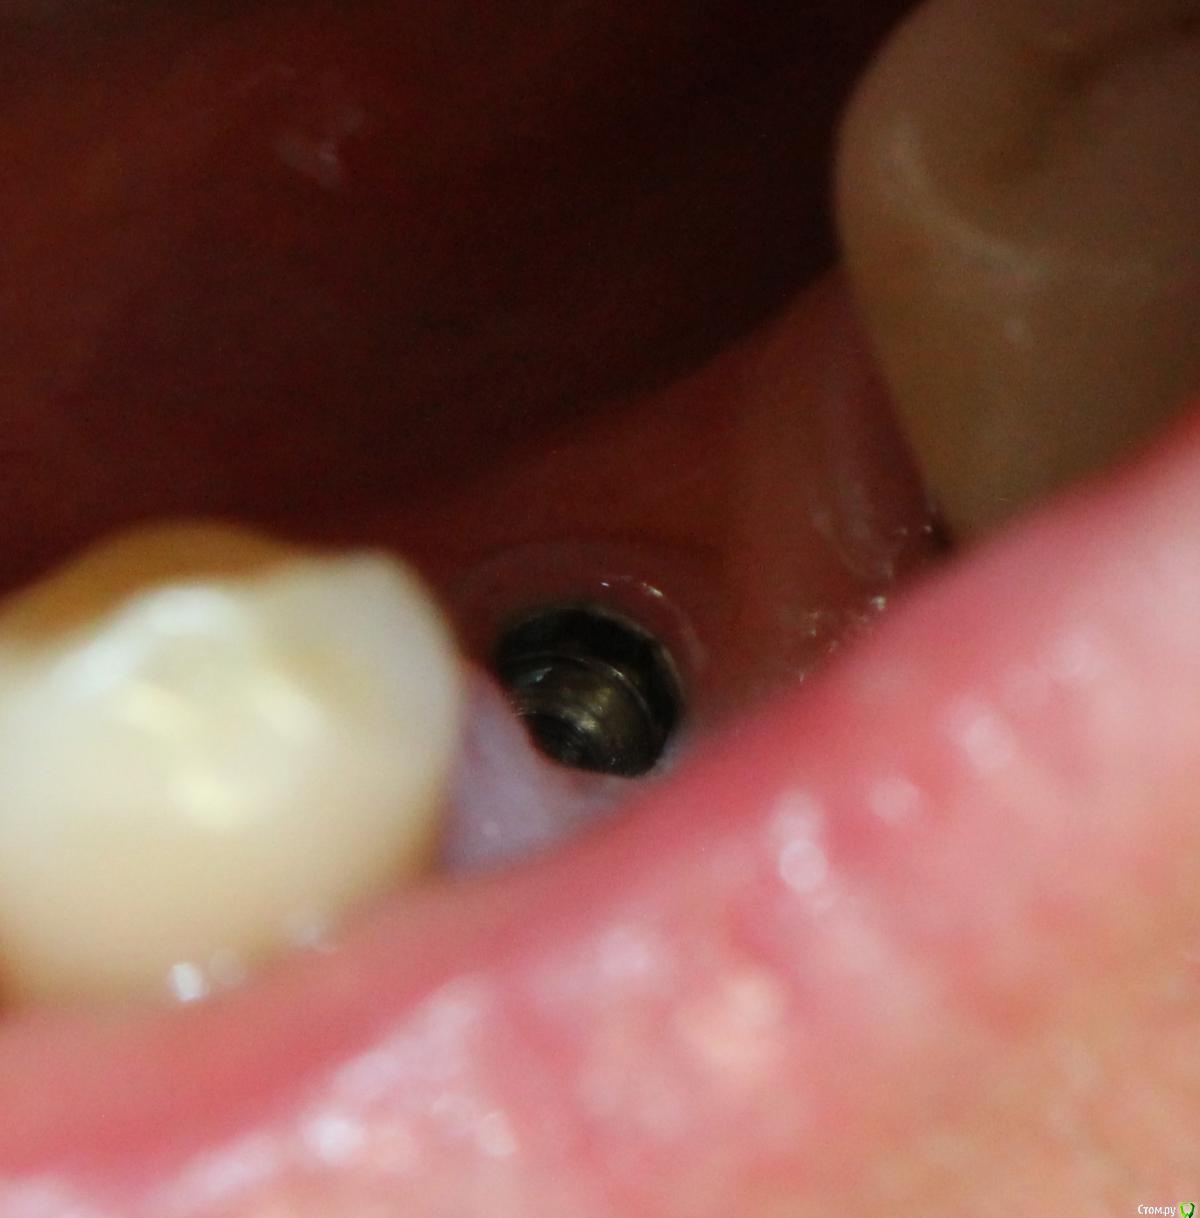

Коллеги добрый вечер. Может кто узнает систему - очень надо, со слов пациента ставил 10 лет назад. Внешне размер платформы примерно 3.5 мм, ключ подошел корейский 1.2, формирователь закрутилс(хоть и не до конца) от Osstem mini/ Внешне напоминает xive или antogyr. Буду очень благодарен.